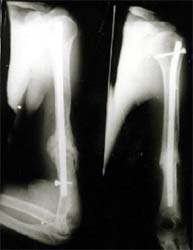

肱骨干骨折 采用闭合穿钉法,带锁髓内钉内固定,10个月后骨折愈合